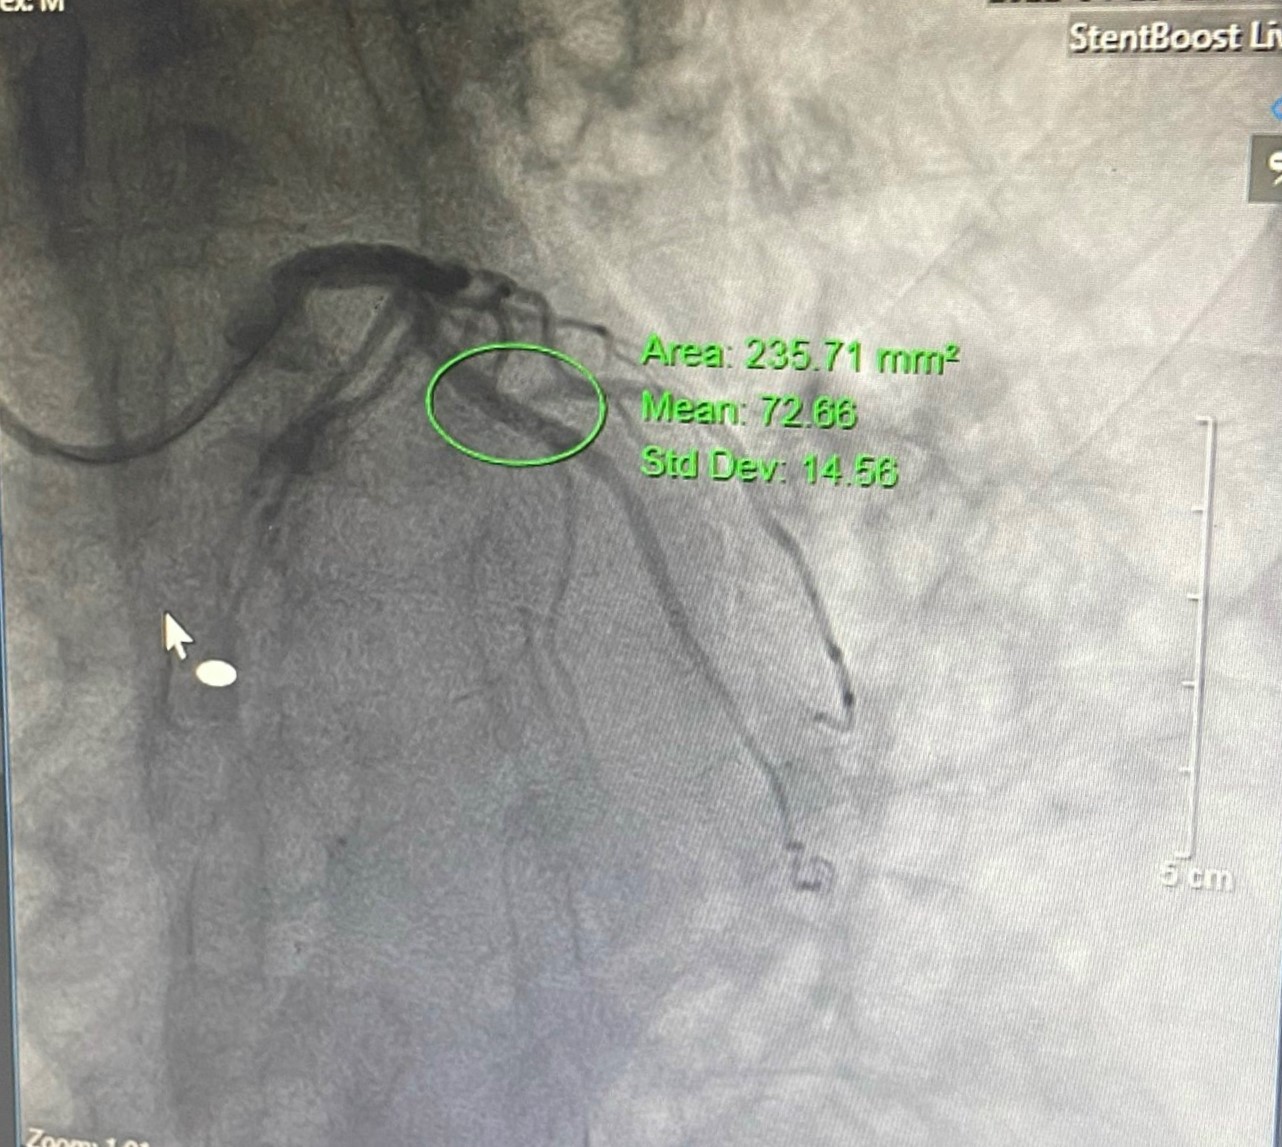

Trường hợp thứ 2 trên bệnh nhân nam 80 tuổi, nửa tháng nay xuất hiện cơn đau thắt ngực không ổn định, tăng khi gắng sức, kéo dài 5-10 phút, khó thở trong cơn. Bệnh nhân có tiền sử COPD, giãn phế quản, tăng huyết áp, tiểu đường. Thực hiện chụp mạch vành qua da phát hiện bệnh nhân có tổn thương rất nặng, hẹp rất khít 2 thân động mạch vành; hẹp 99% liên thất trước (LAD) I-II, xơ vữa gây hẹp 99% động mạch mũ (LCx) I-II. Nếu không can thiệp kịp thời, bệnh nhân dễ dẫn đến nhồi máu cơ tim cấp và các biến chứng nguy hiểm. Bệnh nhân nhanh chóng được xử trí can thiệp, đặt 1 stent mạch vành tại vị trí LCx I-II. Sau can thiệp, bệnh nhân giảm cơn đau thắt ngực, nhánh thứ 2 sẽ can thiệp tiếp khi đã ổn định.